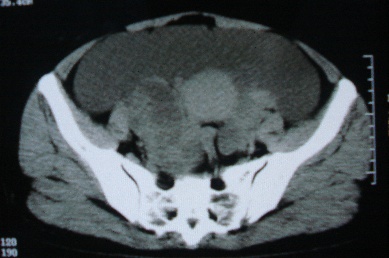

ct10755,女,48岁。感腹胀一周入院。

考虑右侧卵巢囊腺癌并腹腔转移、子宫肌瘤

感觉像是2个病变融合:双侧附件囊腺瘤?

考虑右侧卵巢囊腺癌并腹腔转移可能性大、子宫肌瘤

支持:右侧卵巢囊腺癌并腹腔转移,或囊腺瘤破裂腹腔种植。

支持:右侧卵巢囊腺癌并腹腔转移、腹水、盆腔积液。